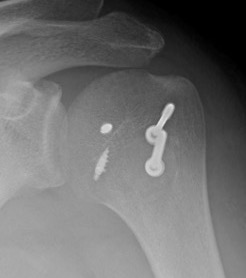

Screw fixation

LT ORIFLT ORIF

Screw + soft tissue washer

LTLTlt

Medial row anchors and lateral screws for missed lesser tuberosity avulsion in adolescent